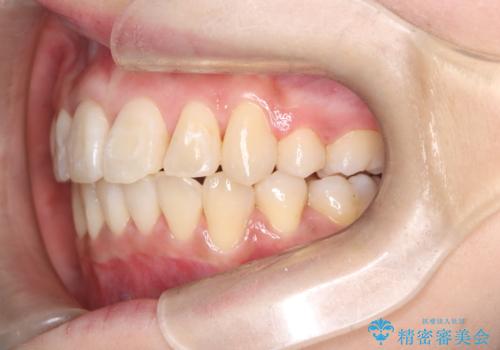

- 八重歯(叢生)と、上下の歯の中心線(正中)がずれていることを主訴にご来院されました。精密な検査の結果、歯列全体のスペースが大幅に不足しており、八重歯を正しい位置に配列し、正中のズレを改善するためには、上下左右の第一小臼歯を抜歯する必要があると診断。装置には、目立ちにくい審美ワイヤーを使用し、見た目を気にせず、機能性と審美性が完璧に整った咬み合わせを目指す治療計画を立案しました。

今回の矯正治療では、まず計画通り上下左右の小臼歯4本を抜歯し、八重歯や正中のズレを解消するための十分なスペースを確保しました。装置には、目立ちにくい白いブラケットとワイヤーを使用した審美ワイヤー矯正を採用。

八重歯: 突出していた八重歯を歯列内に誘導し、デコボコを解消しました。

正中のズレ: 歯を左右対称に移動させることで、上下の歯の中心線を正確に合わせ、顔全体のバランスも改善しました。